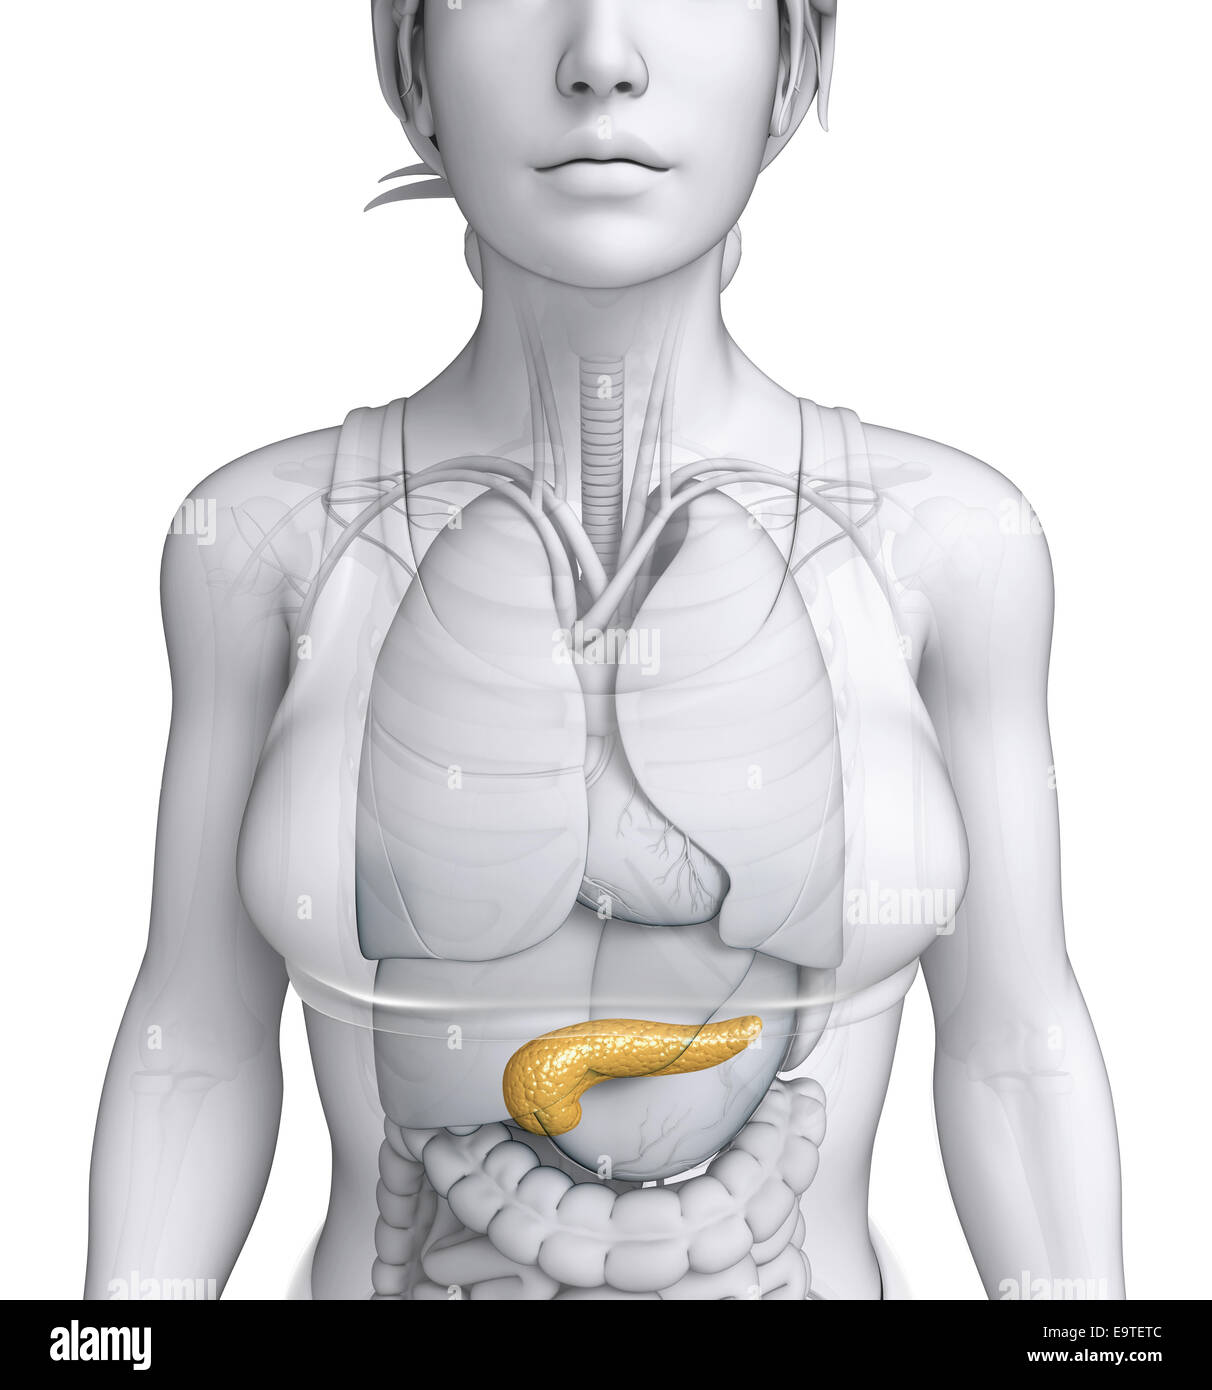

Illustration de l'anatomie du pancréas femelle Banque D'Imageshttps://www.alamyimages.fr/image-license-details/?v=1https://www.alamyimages.fr/photo-image-illustration-de-l-anatomie-du-pancreas-femelle-74911884.html

Illustration de l'anatomie du pancréas femelle Banque D'Imageshttps://www.alamyimages.fr/image-license-details/?v=1https://www.alamyimages.fr/photo-image-illustration-de-l-anatomie-du-pancreas-femelle-74911884.htmlRFE9TETC–Illustration de l'anatomie du pancréas femelle